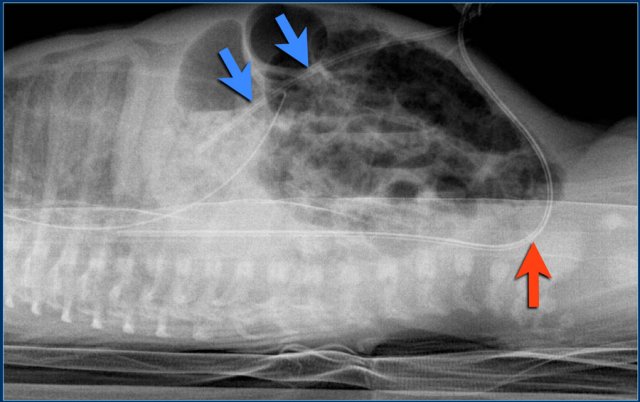

1. This is a lateral horizontal beam radiograph.

It illustrates the umbilical vein line following the traject of the umbilical vein into the liver (blue arrow).

The line is not deep enough.

2. The umbilical arterial line first passes caudally and enters the iliac artery (red arrow).